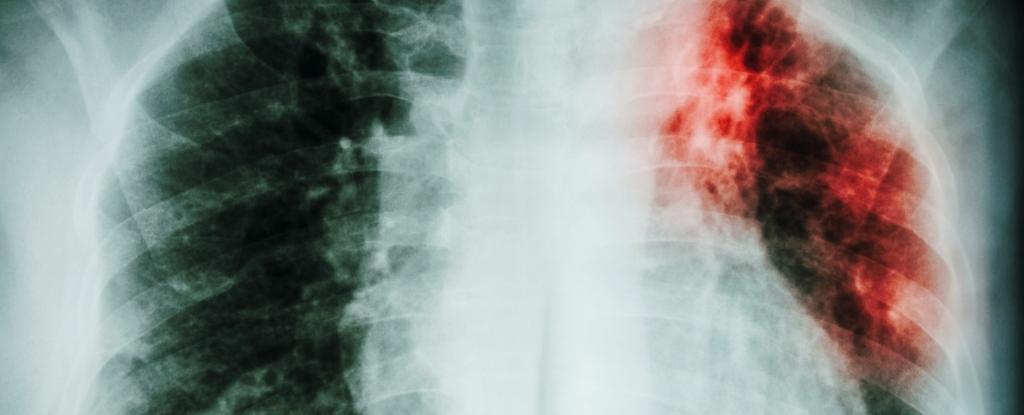

The Unfinished Fight Against Tuberculosis

Despite past successes in reducing tuberculosis (TB) deaths, the disease saw a resurgence in the 1980s and 1990s due to factors like the HIV/AIDS epidemic, drug resistance, and increased migration from high-burden countries. The global burden was underestimated for years, leading to a delayed response. Improved data collection and international efforts have since helped reduce TB deaths, but it remains a major health challenge, especially in lower-income countries. The article emphasizes the importance of good data and sustained global efforts to finally control and eliminate TB.